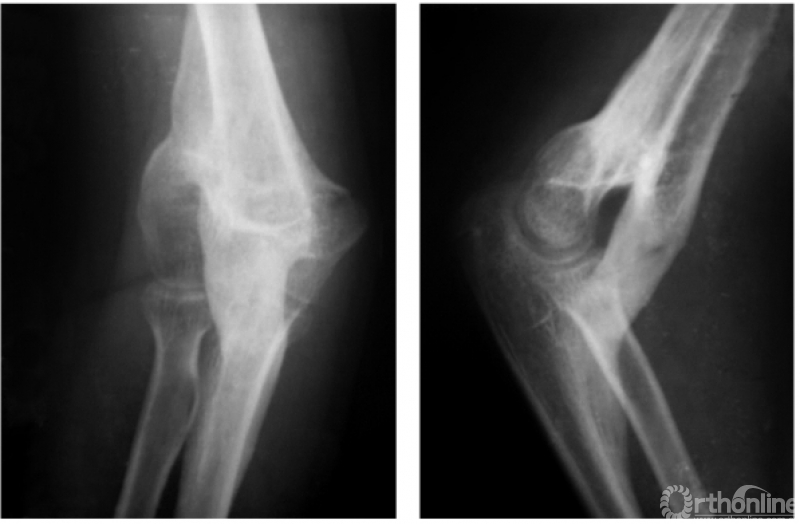

二、陈旧性肱骨髁上骨折

例1:陈旧性伸展型肱骨髁上骨折,致肘内翻畸形及前倾角消失(图7)。

图7

例2:伸展型肱骨髁上陈旧折,完全向后上移位的骨折远端,在被掀起的骨膜下成骨,已为肱骨下段重建了新的关系;而向前下移位的近折端已与尺骨近端形成骨性连接。致患肘被固定在肘曲40°位置上(图8)。

图8